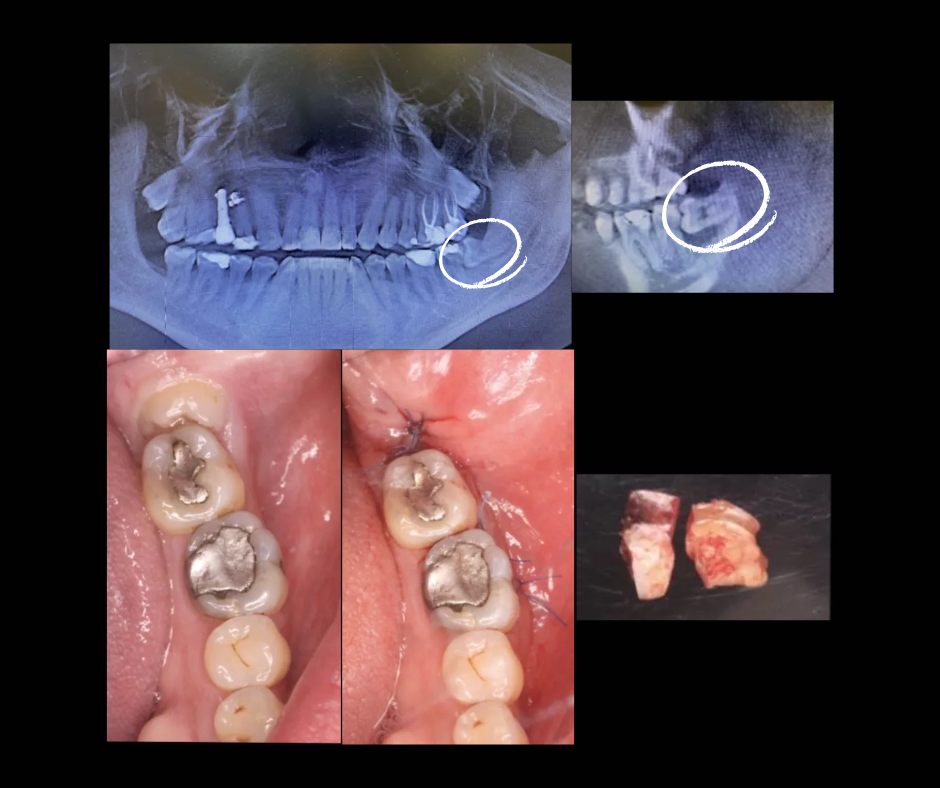

¿Cuándo se recomienda extraerlos?

Tu odontólogo puede sugerir la extracción cuando:

No hay espacio suficiente para su erupción

Están generando dolor o infecciones

Están presionando otros dientes

Presentan caries o fracturas difíciles de tratar

¿Cómo es el procedimiento?

La extracción de terceros molares es un procedimiento seguro, realizado bajo anestesia local y en algunos casos sedación. Con una adecuada técnica quirúrgica, las molestias posteriores son mínimas y recuperarte suele ser rápido.